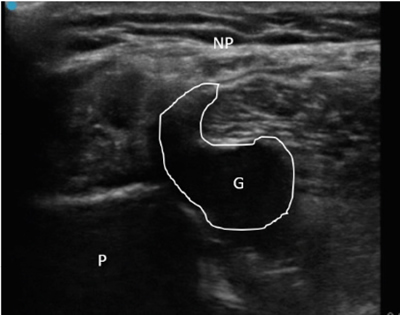

Figura 1

Figura 2